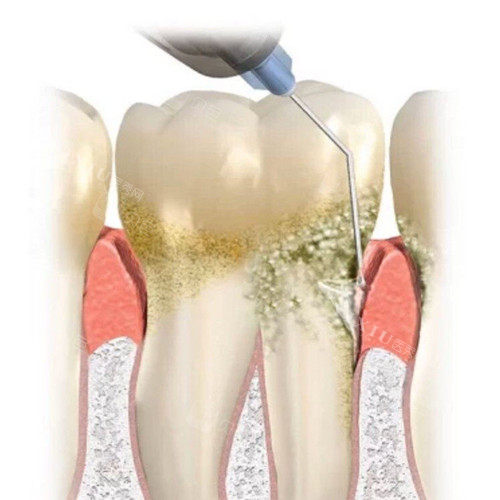

牙齿刮治是一种常见的口腔清洁和治疗方法,主要包括龈上洁治和龈下刮治。龈上洁治也就是我们常说的洗牙,是使用正规器械去除牙龈缘以上的牙菌斑、牙结石和色渍,并磨光牙面,以延迟菌斑和牙石再沉积。而龈下刮治则是用比较精细的龈下刮治器,深入到牙龈以下,刮除位于牙周袋内根面上的牙石、菌斑以及受感染的病变牙骨质,使刮治后的根面光滑平整,有利于牙周新附着的形成。

牙菌斑和牙结石是导致牙龈炎、牙周炎等口腔疾病的根源。牙齿刮治能够有效地将它们从牙齿表面和牙龈下清除,防止这些牙周疾病的发生和发展。如果不及时清除,牙龈炎可能会逐渐发展成牙周炎,比较终导致牙齿松动和脱落。

治疗牙周疾病

对于已经患有牙周疾病的患者,牙齿刮治是控制病情的关键治疗手段。它可以帮助清除深层的牙石和病变组织,减轻牙周组织的炎症,缓解牙龈出血、溢脓、肿痛等症状,促进牙周组织的愈合和再生,防止牙齿松动脱落。